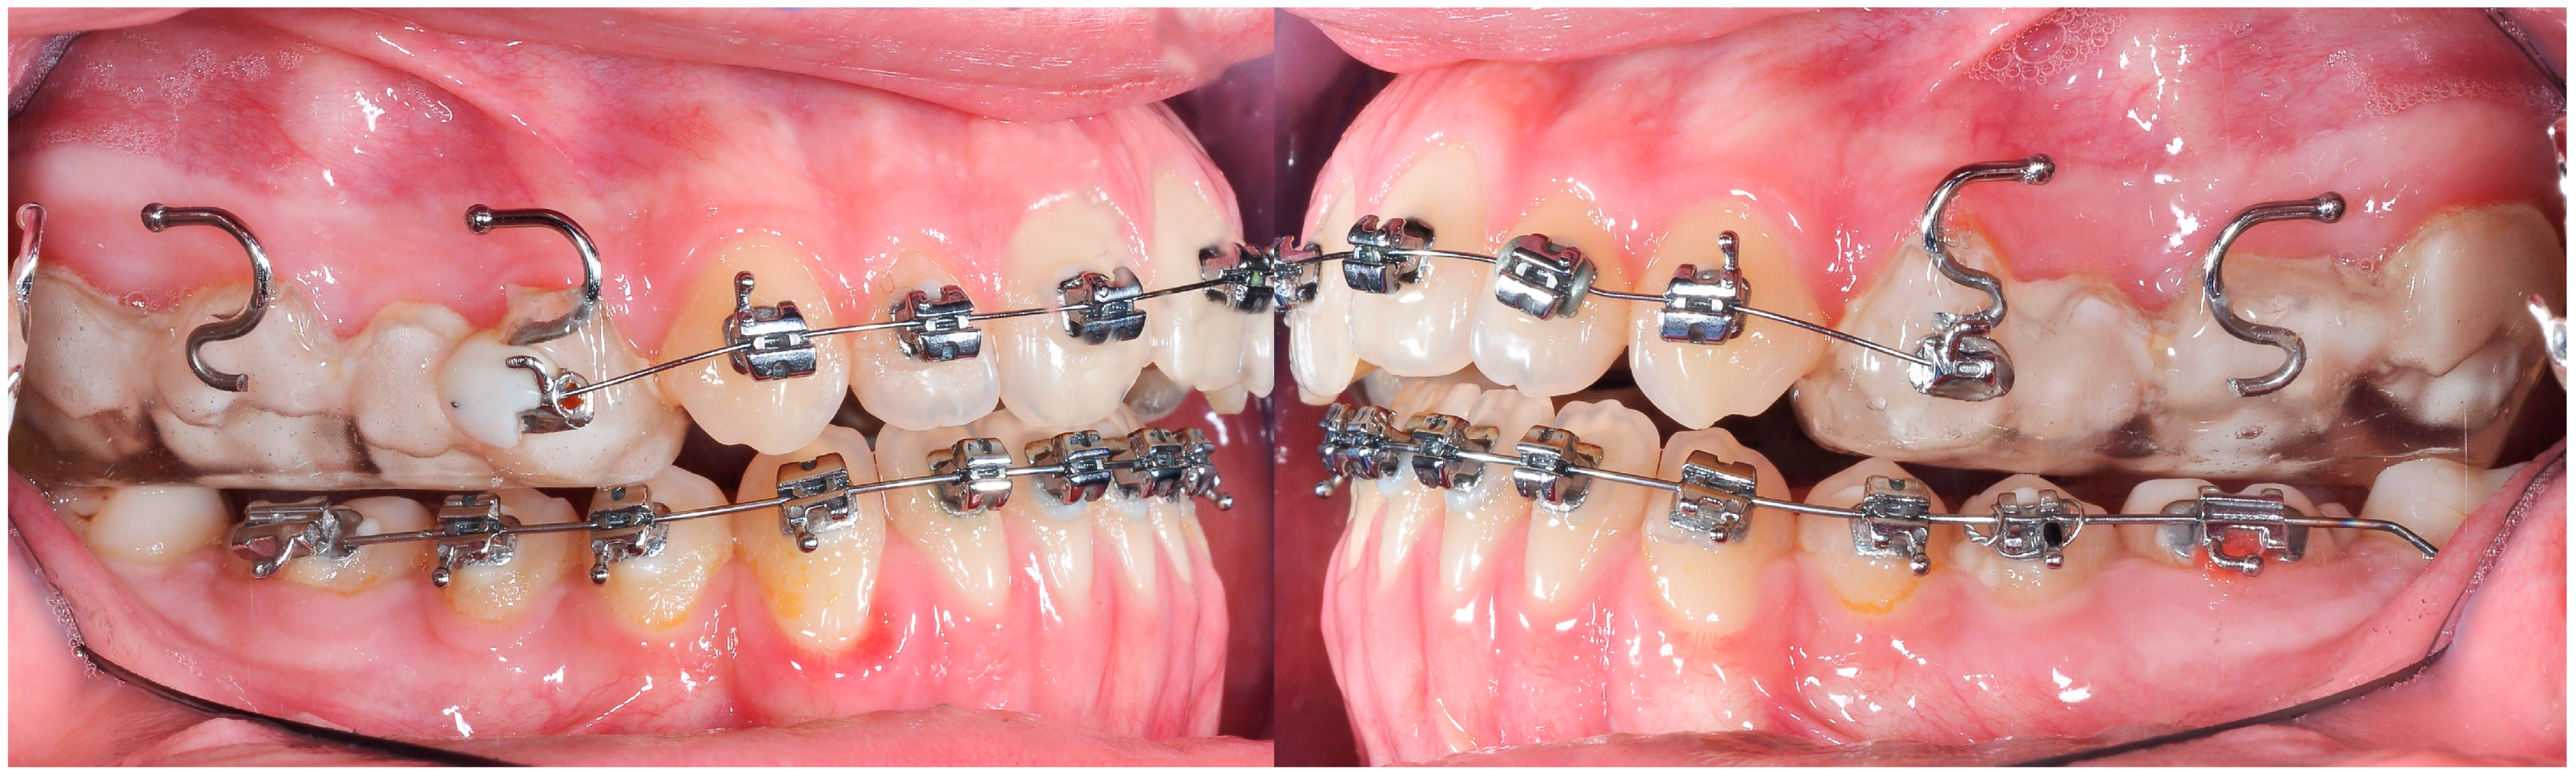

3. The Results of the Treatment